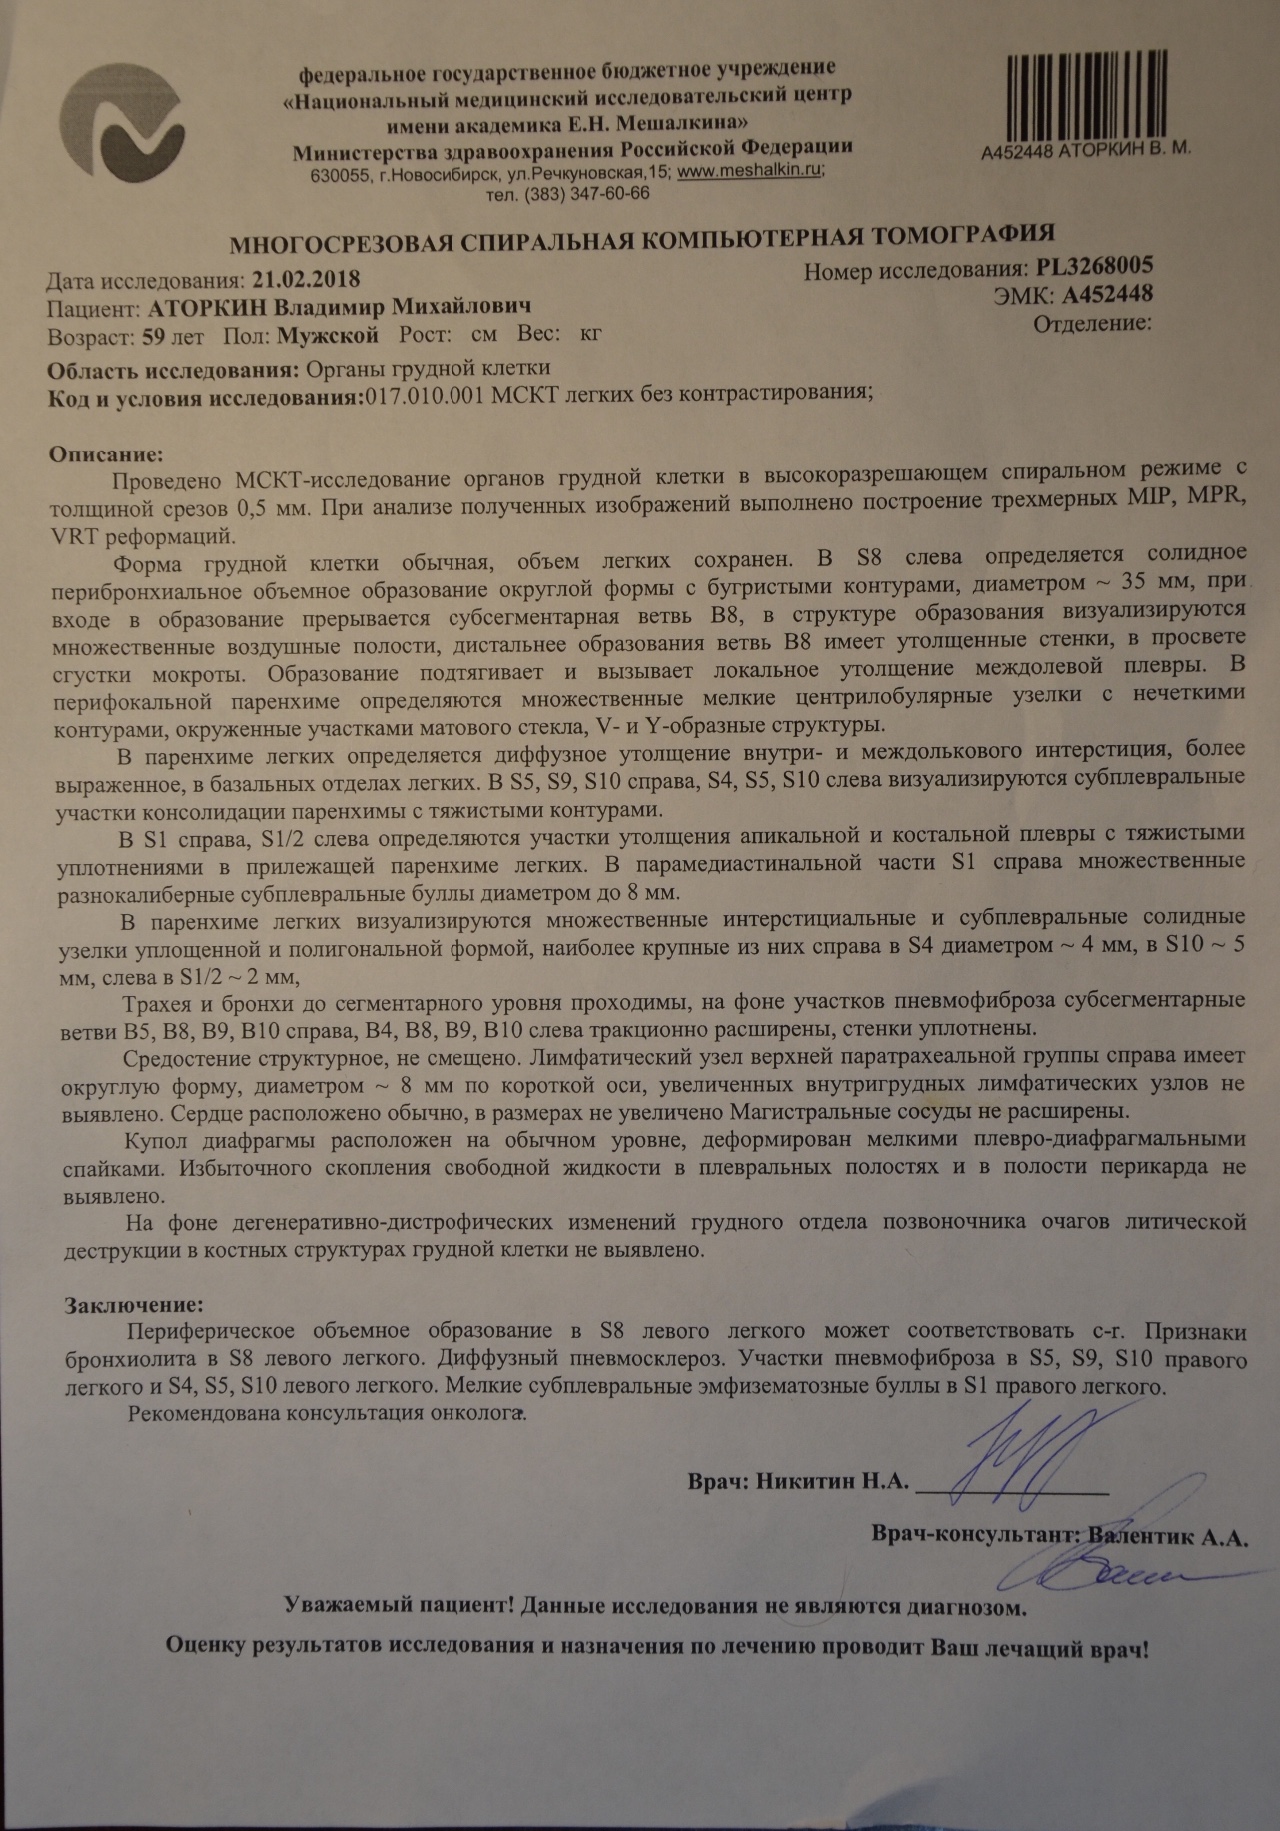

Фотографии и снимки КТ легких без контрастных веществ

Раздел: Визуальный дайджест